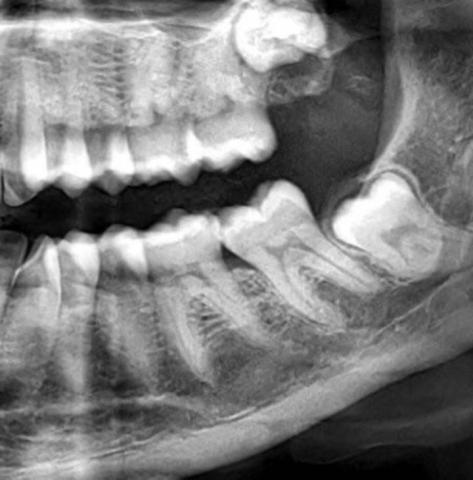

Case Analysis:

Upon examining the dental X-ray, it shows a partially erupted third molar (wisdom tooth) that is horizontally impacted against the adjacent second molar. This type of impaction is known to cause several complications if left untreated.